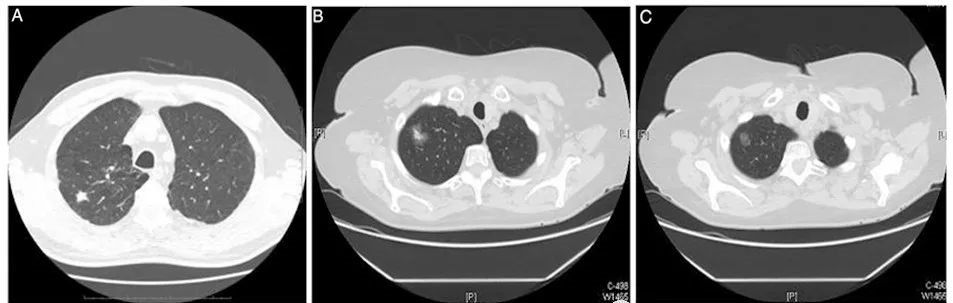

结节的形态分为实性或亚实性,亚实性结节可进一步分为纯磨玻璃结节(无实性成分)和部分实性结节(含有磨玻璃成分和实性成分)。在薄层CT上,根据肺结节的密度大小,将肺结节分为以下三种:

A、实性结节 B、部分实性结节 C、纯磨玻璃样结节